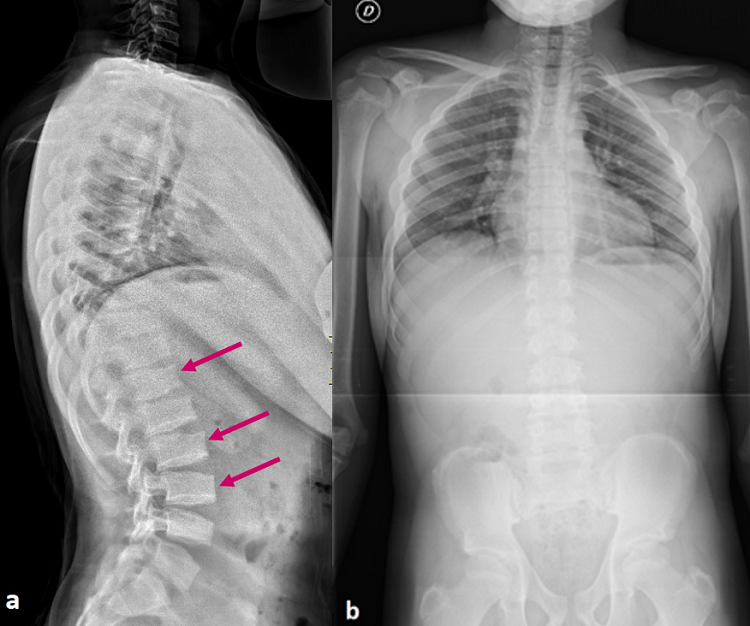

Se realiza estudio de talla baja: bioquímica con perfil hepático, renal y tiroideo normal; anticuerpos antitransglutaminasa negativos; perfil hormonal (IGF1: 213 ng/ml, IGFP3: 4,6 ng/ml, insulina basal: 3 mcU/ml, LH: 2,7 mUI/ml, FSH: 2,34 mUI/ml) con valores normales para edad y sexo; edad ósea de 13 años (que se corresponde con la EC). A la vista de los resultado analíticos normales y de las características de la exploración física, se solicita un estudio radiográfico completo donde se aprecia platispondilia, hiperlordosis lumbar, escoliosis leve (ángulo de Cobb menor de 20°) y dismetría de miembros inferiores (Figuras 1 y 2). Ante la asociación de talla baja desproporcionada de manifestación tardía y las anomalías esqueléticas descritas, se sospecha displasia espondiloepifisaria tardía y se solicita estudio genético, obteniéndose la variante patogénica c.93+5G>A en el gen TRAPPC2 en homocigosis, ligada al cromosoma X. Se realiza estudio genético familiar, siendo la madre portadora de la misma mutación.

Figura 2. a) Radiografía lateral de columna vertebral: se observa platispondilia (cuerpos vertebrales planos) con ¨jorobas¨ en los platillos inferiores y superiores de los cuerpos vertebrales (flechas) e hiperlordosis lumbar. b) Radiografía anteroposterior de columna vertebral: escoliosis leve y asimetría de hombros compensatoria. Mostrar/ocultar